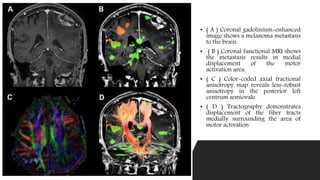

• ( A ) Coronal gadolinium-enhanced

image shows a melanoma metastasis

to the brain.

• ( B ) Coronal functional MRI shows

the metastasis results in medial

displacement of the motor

activation area.

• ( C ) Color-coded axial fractional

anisotropy map reveals less-robust

anisotropy in the posterior left

centrum semiovale.

• ( D ) Tractography demonstrates

displacement of the fiber tracts

medially surrounding the area of

motor activation.